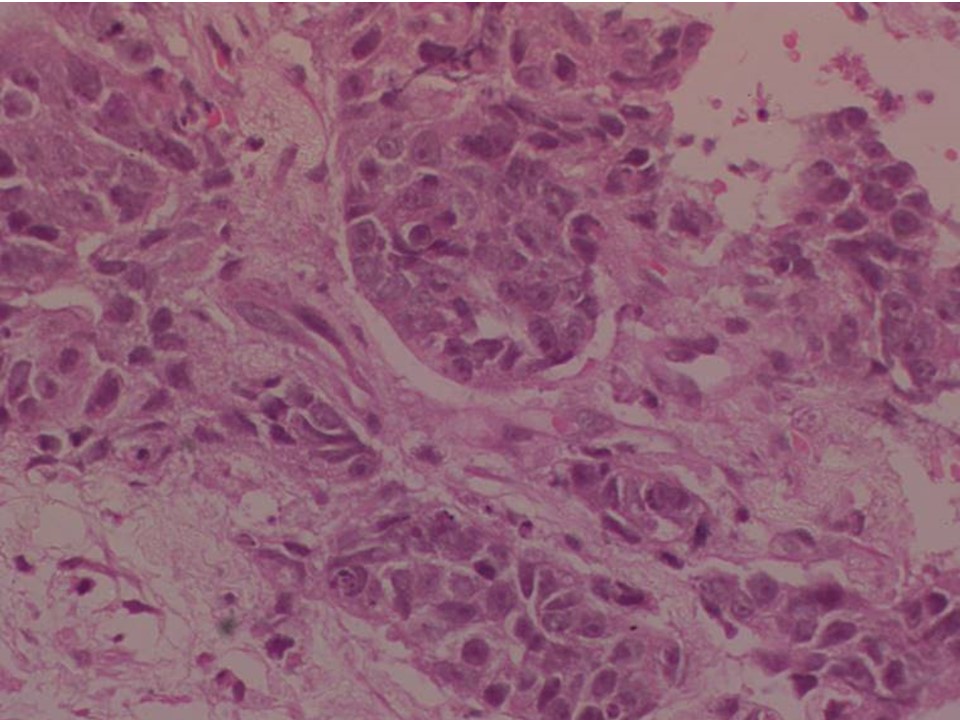

Медицина и диагностика: Инвазивный пузырный занос на УЗИ